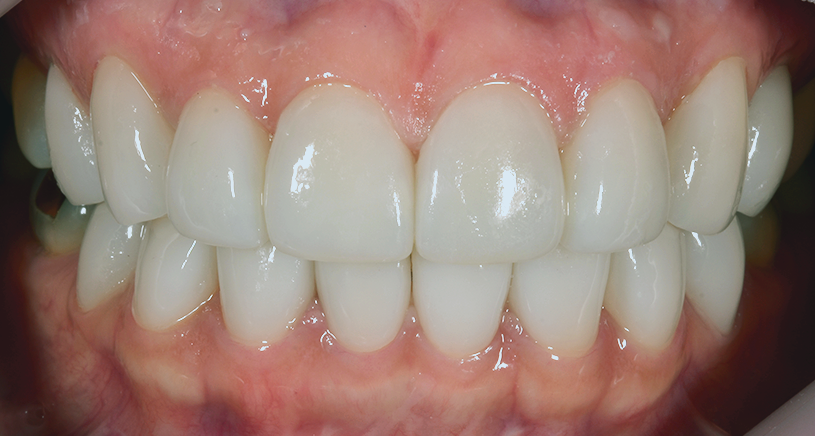

< 사례2 >

블랙트라이앵글 무삭제라미네이트 <블랙필름> 치료 전

블랙트라이앵글 무삭제라미네이트 <블랙필름> 치료 후